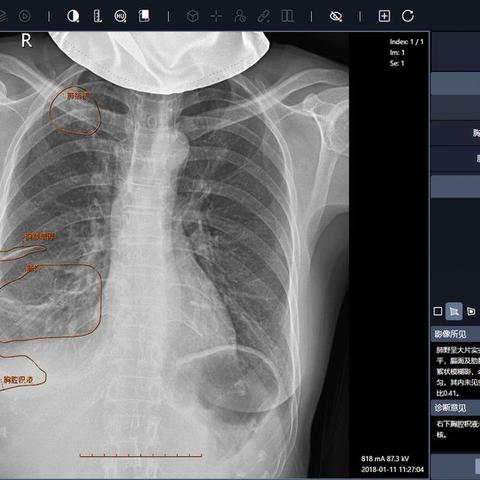

22岁日本演员、写真偶像丰岛心樱的一条社交动态引发全网热议——她晒出一张疑似体检的胸腔X光照片,并配文“我的肺部非常漂亮”,原本聚焦健康的分享,却因影像中清晰的身体轮廓线条,让网友讨论方向彻底偏移:有人留言“线条比肺部更吸睛”,有人调侃“第一次觉得X光片也能看出身材”,相关话题很快冲上热搜。

网友讨论偏移:当健康话题变成外形焦点 这次的X光片分享,原本是丰岛心樱对自身健康状态的轻松展示,但网友的注意力却很快从“肺部健康”转移到“身体轮廓”——X光片里清晰勾勒出的肩颈线条、胸腔曲线,被不少人拿来讨论“身材管理的细节”,甚至有粉丝调侃“这是最特别的‘身材秀’”,这种偏移并非偶然:在社交媒体时代,偶像的任何分享都可能被放大解读,而丰岛心樱作为写真偶像的“颜值标签”,更让网友不自觉地将注意力聚焦在“外形相关”的细节上——哪怕是一张看似“无关颜值”的医疗影像,也能被粉丝挖掘出与“偶像魅力”相关的内容。